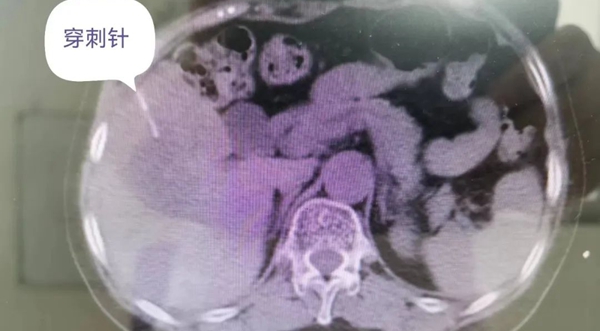

做好術(shù)前準(zhǔn)備后,患者入CT室,由普外二科主任張玉衛(wèi)帶領(lǐng)的科室人員及麻醉科、影像科骨干人員等組成的手術(shù)小組成員全部準(zhǔn)備到位。手術(shù)開始,患者取平臥位并負(fù)壓體位固定墊固定好,CT平掃后確定肝右葉腫物位置,局部浸潤麻醉成功后再次CT掃描,確定活檢套管針穿刺位置及深度,調(diào)整套管針,使針尖距腫瘤外緣約5mm,活檢槍取出組織條4條。去除穿刺針,復(fù)查CT檢查無腹腔積液。

肝腫物穿刺中影像圖像